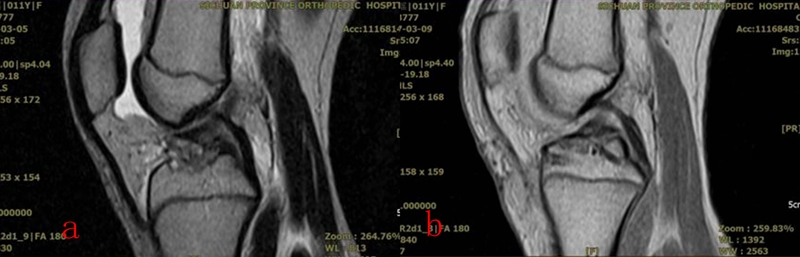

从2016年4月~2020年12月,共计25名4~11岁患儿接受了镜下手术,平均年龄9.2岁。在全部患儿中,有10名病程超过两周,属陈旧性骨折。作者采用了肩袖的镜下缝合桥技术,通过术中透视,所有的操作均在生长板上完成:在骨床后壁胫骨内、外侧髁间嵴连线中点植入一枚内排锚钉,用成角90°半月板全内缝合器将0号PDS线环在前叉韧带后内、后外两侧穿过撕脱骨块,将锚钉自带两种颜色的双骨科高强缝线分别从前叉韧带两侧过线穿过线环,并牵拉穿过撕脱骨块到达骨折表面。再将双色缝线混合引入胫骨骨床提前钻好的两个骨隧道中,双向交叉压迫于撕脱骨块上,调整骨位及缝线位置并拉紧缝线后,完成镜下复位。拉出胫骨隧道后的缝线使用一枚外排钉固定于生长板上。术毕,镜下缝线桥复位及内固定如图1所示,术前及术后MRI如图2和图3所示。术后2~3天,在疼痛缓解的前提下,开始主动康复训练。

图2 a:术前MRI;b:术后MRI